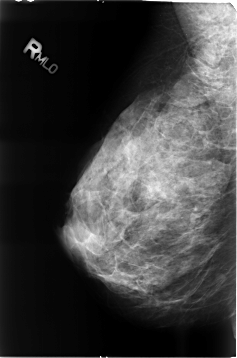

B_3456_1.RIGHT_MLO

RIGHT_MLO LINES 4648 PIXELS_PER_LINE 3080 BITS_PER_PIXEL 12 RESOLUTION 50 NON_OVERLAY